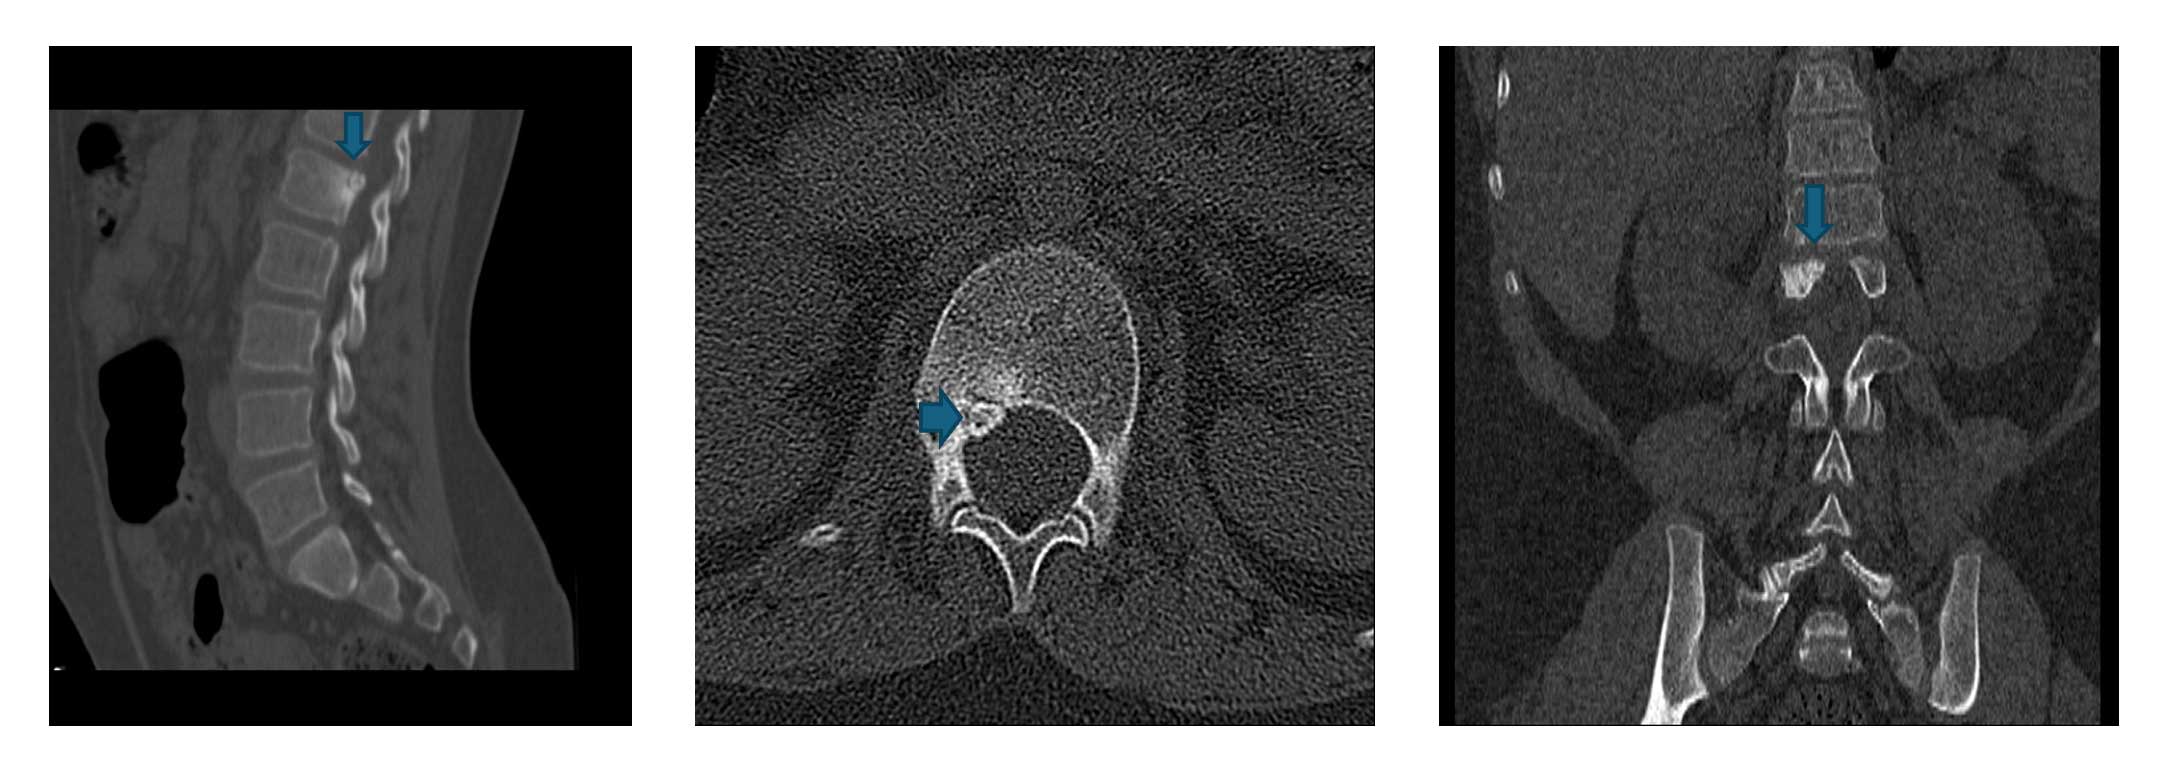

Tomografi kesitlerinde tipik nidus saptandı

Kesin tanı: Osteoid Osteoma (L1 yerleşimli)

Ameliyat Öncesi: Tomografide birinci lomber omurga sağ taraf yerleşimli osteoid osteoma için tipik nidus görülmekte.